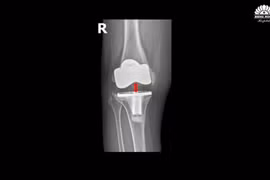

(khoahocdoisong.vn) - Tổn thương khớp gối do bệnh lý hoặc chấn thương mà điều trị bảo tồn không kết quả, bệnh nhân đau không đi lại được, mất chức năng khớp gối thường được chỉ định thay khớp gối nhân tạo.

Các loại khớp gối nhân tạo hiện nay có hạn sử dụng khoảng 15 đến 20 năm. Tuy nhiên, tuổi thọ của khớp gối nhân tạo còn phụ thuộc vào tần suất, mức độ sử dụng, vận động của người bệnh. Cần tránh sự tổn hại khớp sau thay.